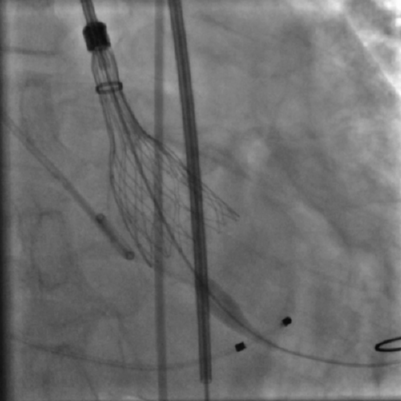

术中影像

主动脉根部造影和冠脉造影+PCI

瓣膜稳定释放和瓣膜释放后左冠显影正常